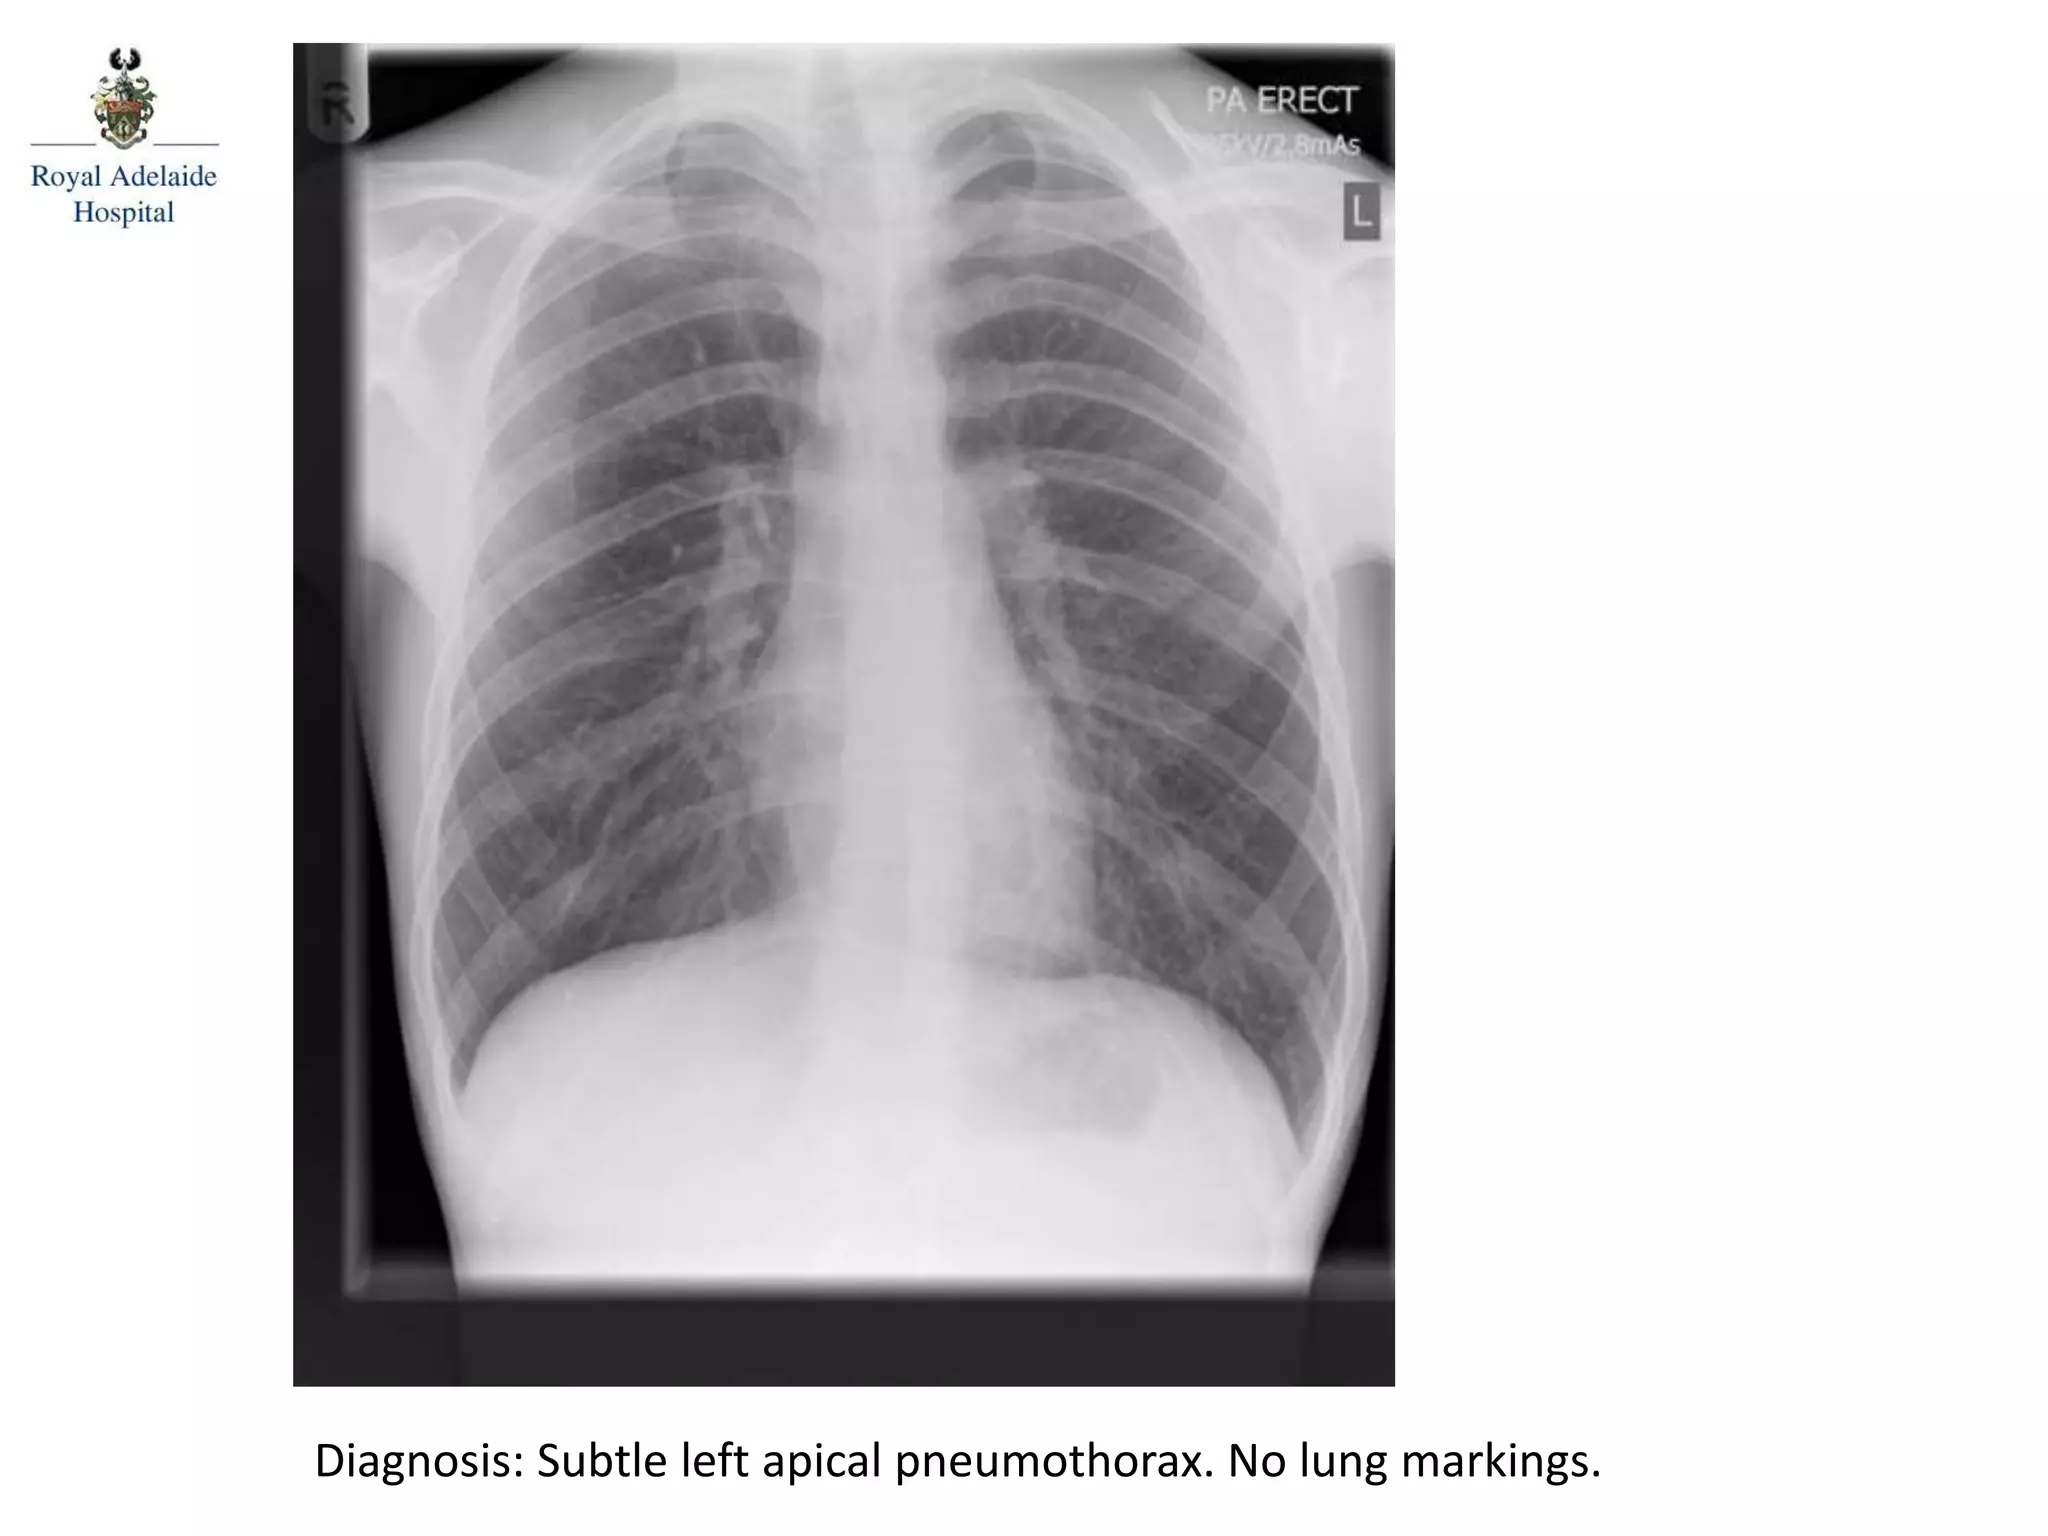

Diagnosis: Subtle left apical pneumothorax. No lung markings.